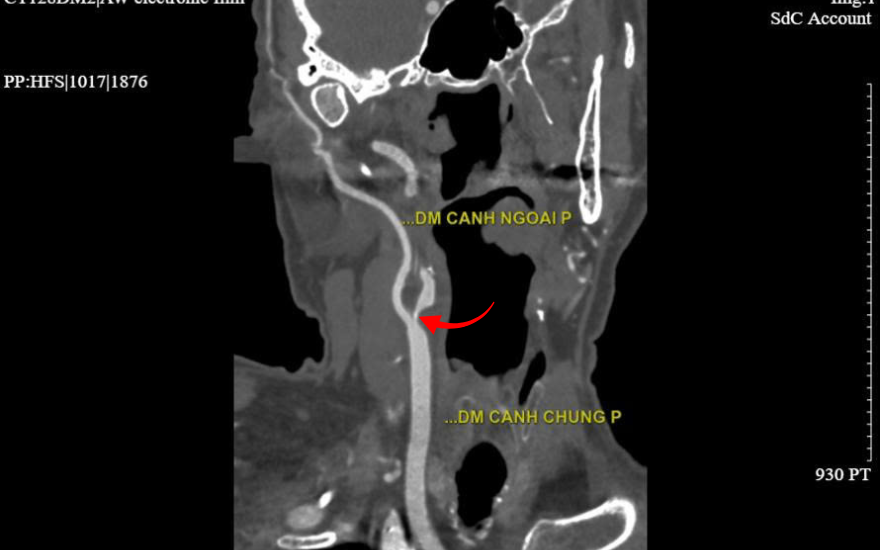

Subsequent paraclinical test results revealed severe stenosis (>90%) of the right internal carotid artery at its origin, accompanied by multiple atherosclerotic plaques. In addition, the coronary arterial system was also found to have over 90% stenosis in the left anterior descending (LAD) artery.

The site of carotid artery stenosis on the 2560-slice CT imaging.

Severe carotid artery stenosis, which reduces or obstructs blood flow to the brain, was identified as the underlying cause of the dangerous symptoms experienced by Mr. Halpern. Dr. Hung warned: “If the arterial lumen is not promptly revascularized, the patient may face a cerebrovascular accident (stroke) with severe sequelae such as paralysis, speech impairment, cognitive decline, and even life-threatening complications.”